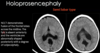

TECTAL GLIOMAS

major points

4TH VENT OBSTRUCTION:

-causes?